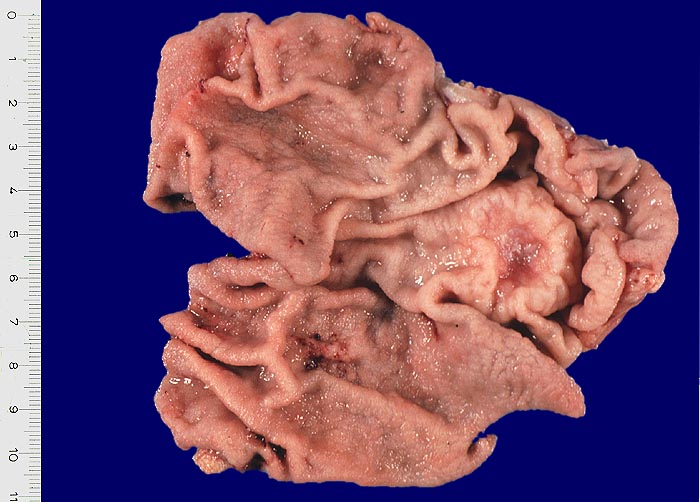

Makroskopie

Befund

Pathologischer Befund

Normalbefund

• Am unteren Ende des Präparates Antrummukosa mit mässiggradiger chronischer, geringgradig aktiver Gastritis und ausgedehnter intestinaler Metaplasie (Becherzellen).

• Weiter oben Invasion der Magenschleimhaut durch ein teils solides, teils drüsenbildendes Adenokarzinom mit stark atypischen Tumorzellen.

• Fokale Erosion des Karzinoms bedeckt von fibrinoleukozytärer Membran.

• Tumorinfiltration der Submukosa an der oberen Präparathälfte.

• Der invasive Karzinomanteil zeigt teilweise muzinöse Differenzierung (teils siegelringzellige Tumorzellen schwimmen in extrazellulären Schleimseen).

• Tumorfreie Lamina muscularis propria.